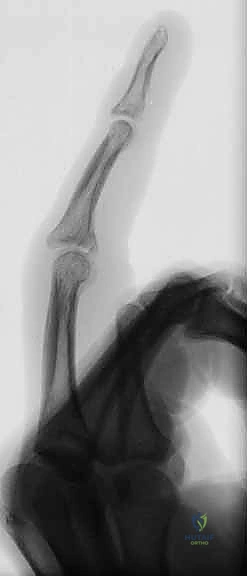

الحالة الأولى: كسر خلع ظهري مفتت بشدة

- قبل الجراحة: تظهر الأشعة خلعاً تاماً للمفصل مع تفتت شديد في قاعدة السلامية الوسطى.